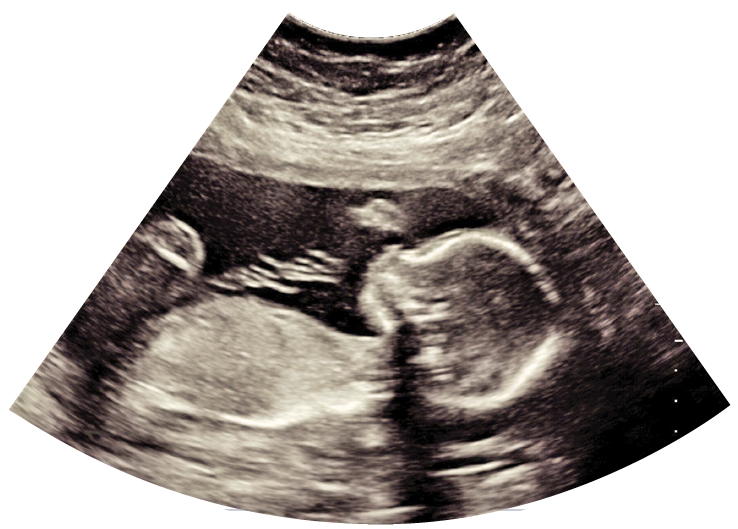

În ultimele decenii, examinarea ecografică a avut un impact dramatic în practica obstetricală și în medicina perinatală, oferind informații importante pentru înțelegerea dezvoltării structurale și fiziologice a fătului încă din stadiile timpurii ale sarcinii. Este ușor de înțeles utilizarea extinsă în obsterica modernă a acestei tehnici, promovată de valoarea și siguranța sa, care au condus la o listă lungă de indicații la femeile gravide. Evoluția științifică din ultimele decade a demonstrat faptul că multe complicații ale sacinii sunt potențial detectabile încă de la evaluarea de la sfârșitul primului trimestru, încurajând inversarea piramidei pentru îngrijirea prenatală, bazată de această dată pe evaluarea inițială de la 11-13 săptămâni gestaționale. Astfel, pe baza combinației dintre caracteristicile materne, constatările examinarilor ecografice din primul trimestru și determinări biochimice din sângele matern, au fost dezvoltați algoritmi eficienți în predicția celor mai importante aneuploidii (număr de cromozomi diferit de cel normal), a avortului spontan și morții fetale intrauterine, nașterii premature, preeclampsiei (riscul de pierdere a cunoștinței de către femeia gravidă la sfârșitul sarcinii sau la expulzarea fătului, crampe, vomă, comă), diabetului gestațional, restricției de creștere și macrosomiei (gigantism).

În ultimul deceniu se discută tot mai mult despre faptul că examinarea ecografică de la finalul primului trimestru tinde să devină prima evaluare structurală a fătului. În cazul detecției unor anomalii structurale severe, se oferă astfel posibilitatea avortului terapeutic mai devreme și mai în siguranță, cu costuri și impact emoțional mai mici.

Practic, se realizează un transfer important al ratei mortalității fetale către primul trimestru, fiind cunoscut faptul că anomaliile fetale majore reprezintă 25% din decesele neonatale și pot conduce la dizabilități pe termen lung, precum și costuri socio-economice considerabile. Totuși, o evaluare amplă a anatomiei fetale la examenul ecografic din primul trimestru depinde de disponibilitatea unui personalul calificat și a unor echipamente ecografice performante, de protocoalele locale de examinare, de considerații legale și rambursarea costurilor de către sistemele de asigurare de sănătate. În ceea ce privește evaluarea morfologică fetală, politica actuală a majortității sistemelor de sănătate oferă o examinare ecografică transabdominală de rutină efectuată de personal competent la 18-23 saptămâni de gestație, alocându-se 20 minute pentru examinarea sistematică detaliată a fătului. Anomaliile structurale, chiar majore, pot fi inaparente în primul trimestru; așadar, valoarea examinării ecografice standard din trimestrul al doilea rămâne fundamentală, întrucât reprezintă o examinare de bază, care trebuie comparată cu examinările anterioare sau ulterioare pentru evalurea stării fetale. În consecință, discuțiile actuale nu contestă valoarea ecografiei precoce detaliate, ci mai degrabă justificarea din punct de vedere cost-beneficiu. Dacă dorim beneficii certe, sistemul medical trebuie să asigure echipamente corespunzătoare, sonografiști calificați și audit.